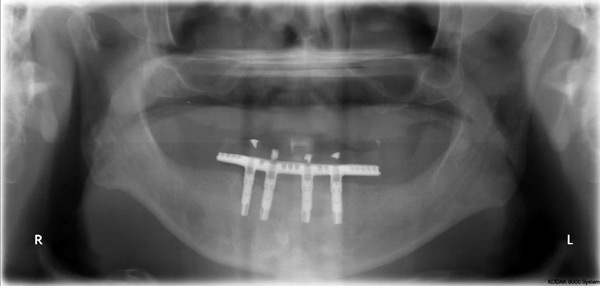

Case Study 3

Problem: This gentleman had an accident with a four-wheeler which gave him multiple jaw fractures and broken teeth. As a result of his accident, it left him with no teeth in the upper and lower front.

Plan: Our plan… the fractures were fixed and three implants were placed on the upper arch and two implants on the lower arch bridging the missing teeth. We also fixed a few broken teeth with root canals and crowns.

Don’t let accidents ruin your smile.